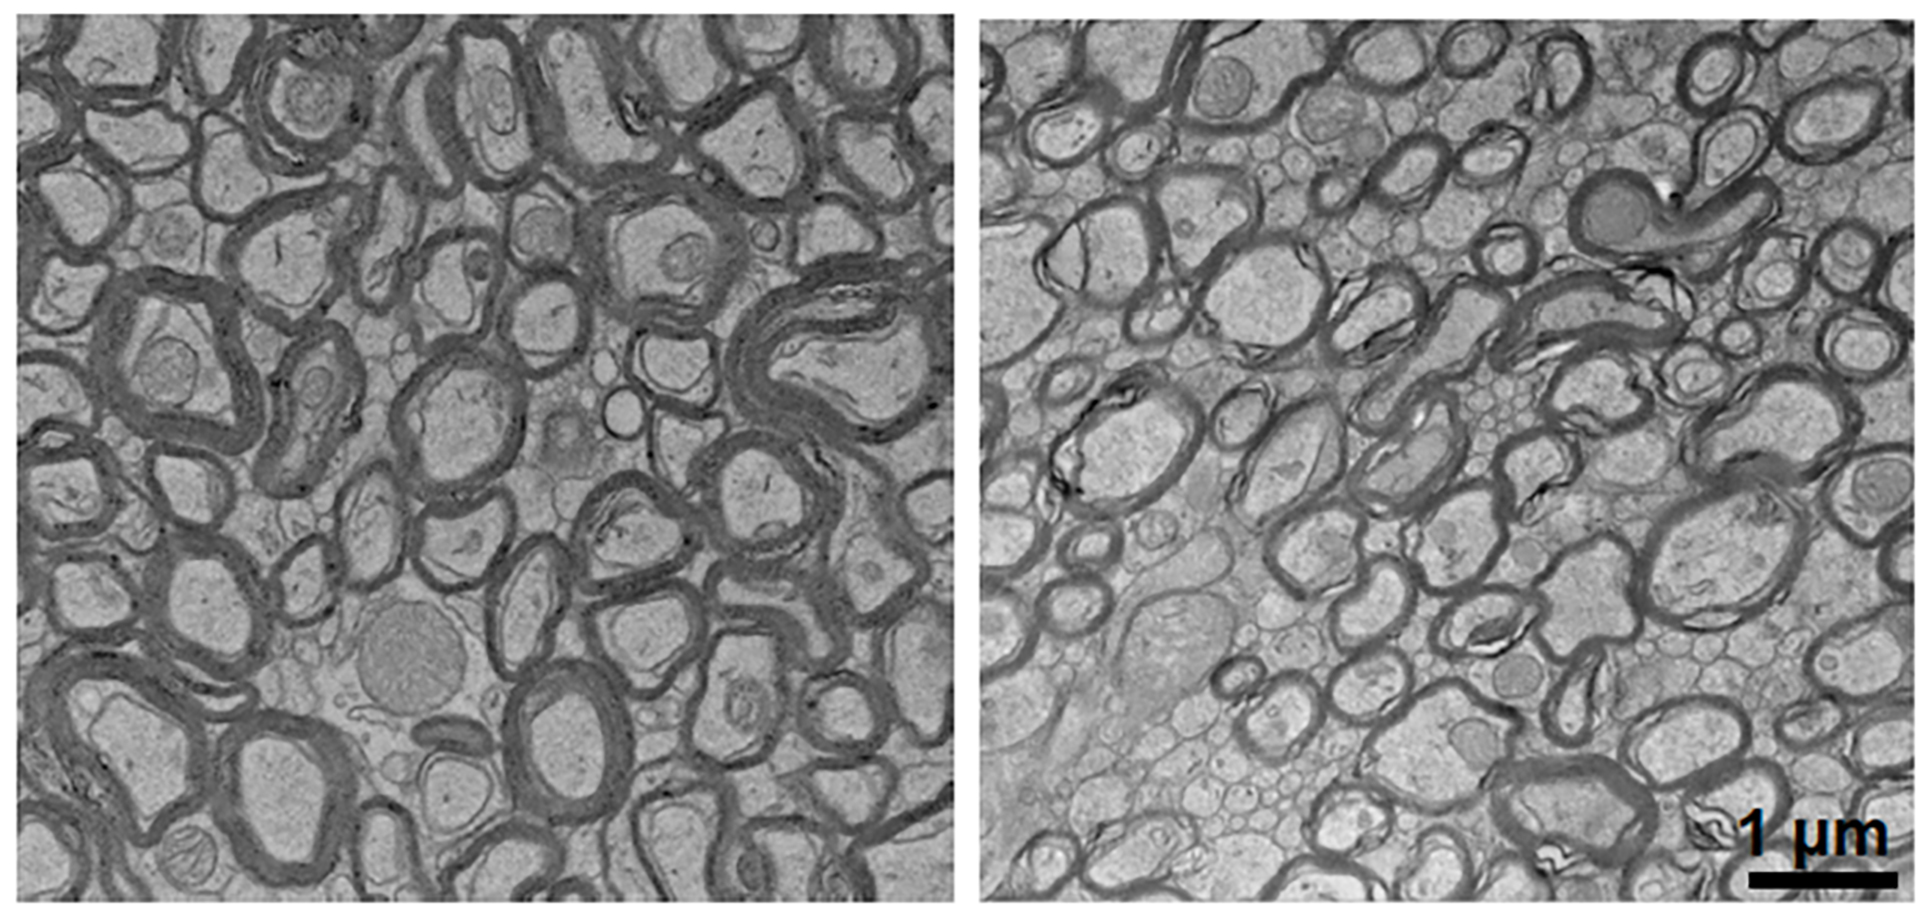

Lithium deficiency thinned the myelin that coats neurons (right) compared to normal mice (left).

Yankner Lab